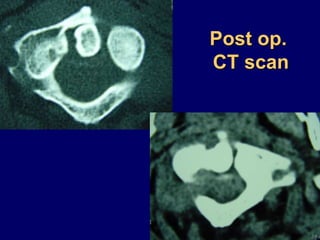

Post op.

CT scan